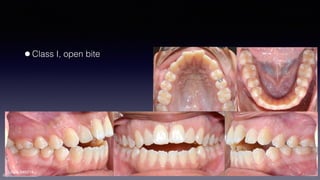

•Class I, open bite

•Severe ALD

•Bimaxillary protrusion